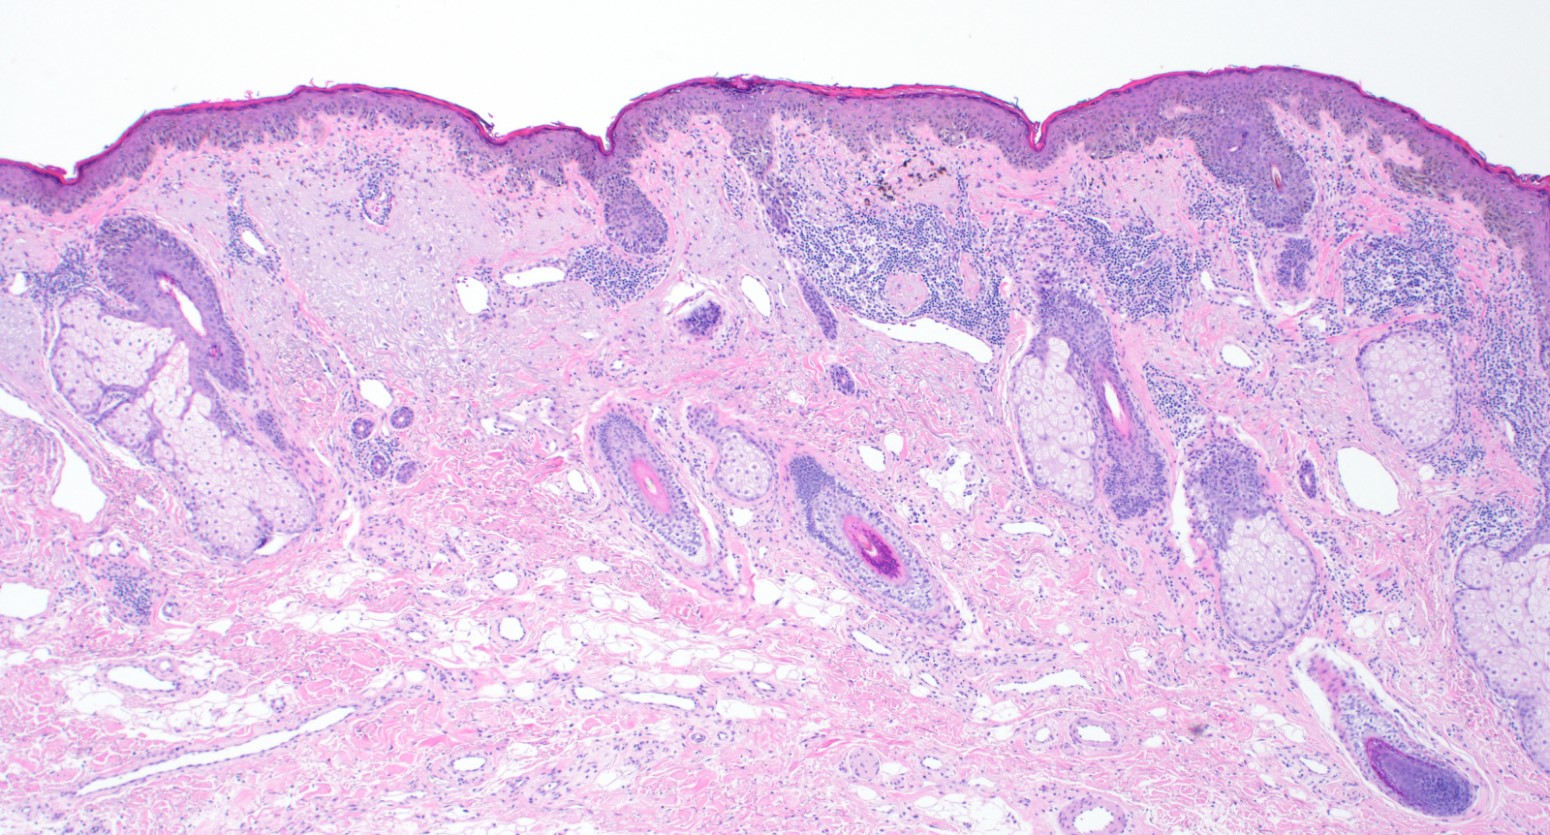

Microscopic (histologic) description

- Proliferation of intraepidermal (single and nested) melanocytes overlying solar elastosis

- Melanocytes demonstrate crowded growth along the basal epidermis

- Associated epidermal alterations, including loss (effacement) of epidermal rete and associated irregular epidermal hyperplasia

- Pagetoid scatter (melanocytes above the basal layer)

- Involvement of adnexal epithelium

- Melanocytic cytology is variable, ranging from small cells with dark nuclei and scant cytoplasm to epithelioid pigmented melanocytes, to spindled melanocytes

- Invasive component, if present, consists of single or nested melanocytes in the dermis with similar cytologic features to those in the in situ component (Cancer Res 1969;29:705, Am J Pathol 1969;55:39)

Microscopic (histologic) images

Contributed by Joseph Gillam, M.D., Jennifer Crimmins, M.D. and Mark Mochel, M.D.